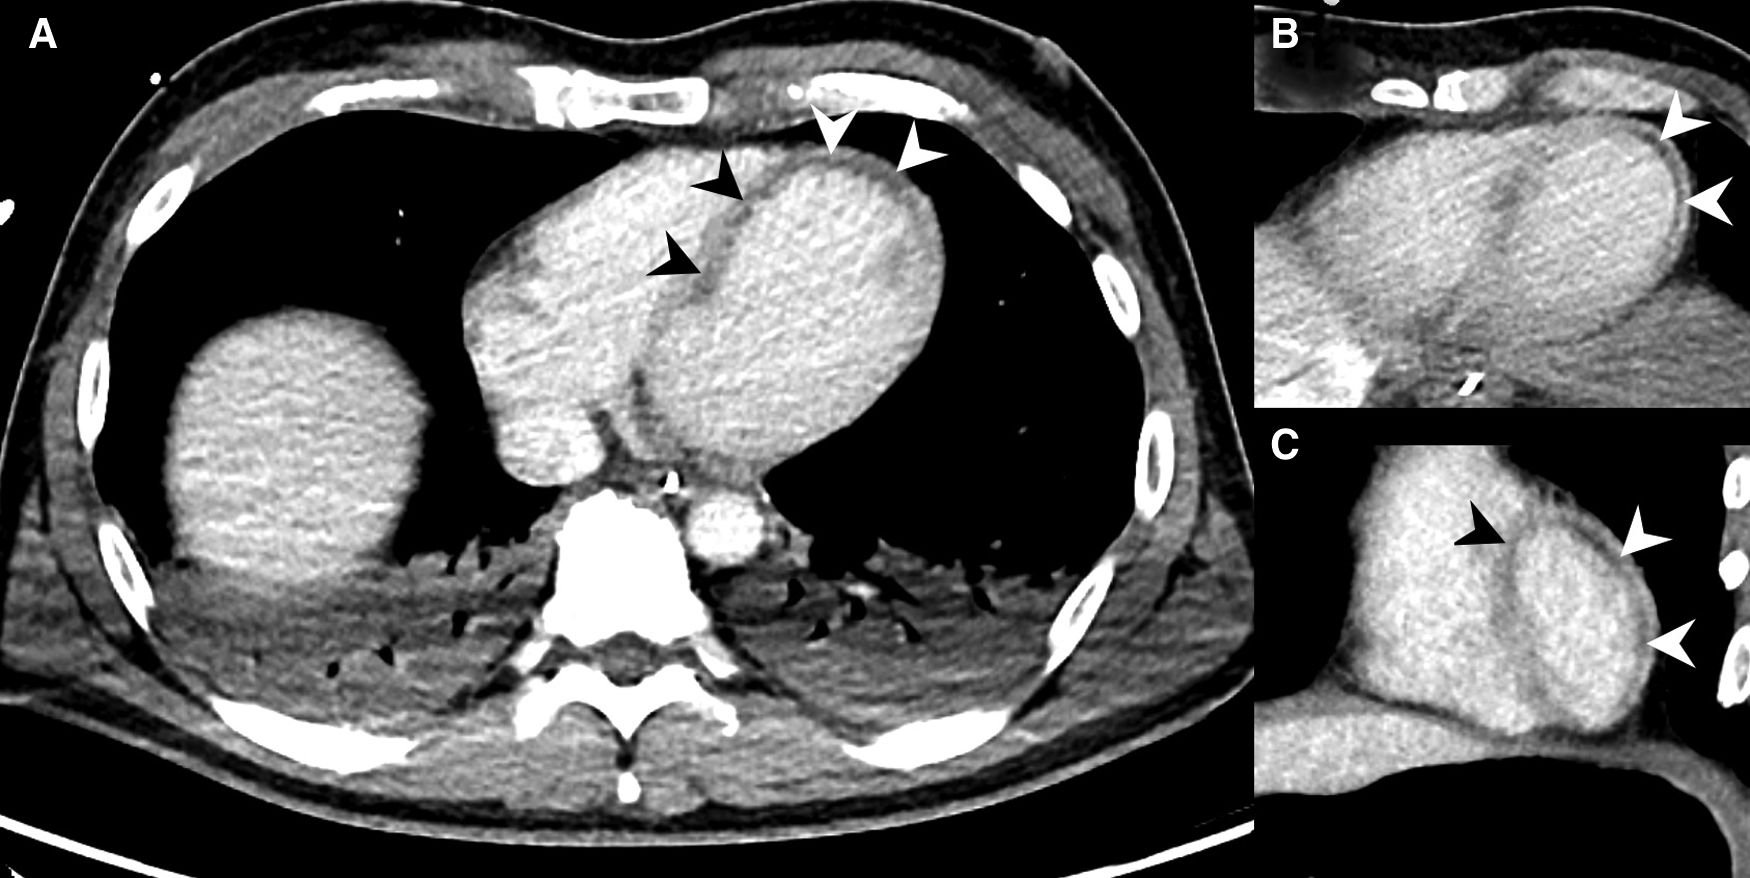

Figure 7

Collection of MDCT images of patients with MH (black and white arrowheads) caused by acute MI. (A) Slight subendocardial perfusion deficit at the heart apex. (B) Coronal slice through the heart base showing predominately subendocardial MH. (C) Extensive MH at the left ventricle. (D) Coronal reformats with impressive MH at the cardiac apex. (E) Axial MDCT slices demonstrating MH at the cardiac apex. (F) Subendocardial MH along the entire left ventricle.